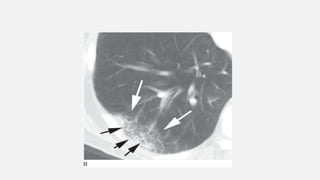

• #12  image of the right lung showing numerous ill-defined nodules in a patient with disseminated pulmonary tuberculosis.

• #14 Ground-glass opacification on CT in an immunocompromised patient with Pneumocystis jiroveci infection.